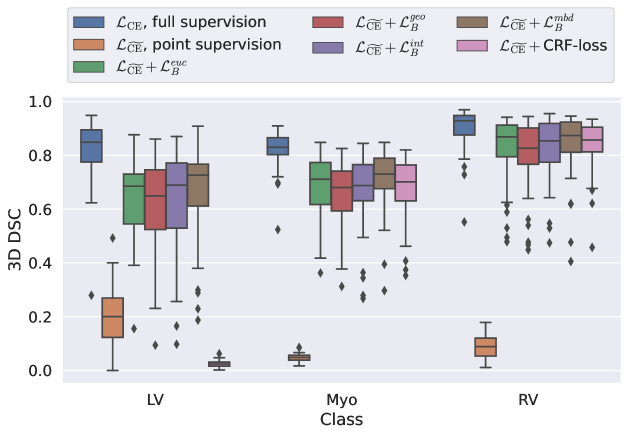

5.1 Segmentation of cardiac structures

The average 3D Dice scores and HD95 values on the ACDC test set are given in Table 2, and boxplots in figures 4 and 5 show the distributions. We see that, in terms of DSC, the proposed strategy of using intensity-aware distances withing boundary loss performs better than simply using the Euclidean distance, with the best results achieved by using the strictly intensity based MBD. The HD95 however favors the original version of , which may be do to its smoother predictions and less fragmentation and oversegmentation. The CRF-loss results are significantly worse in both metrics.

LABEL:\pgfplotslegendfromnamecommon

| Method | RV | Myo | LV | All |

|---|---|---|---|---|

| (fully supervised) | ||||

| (point annotations) | ||||

| w/ CRF-loss [33] |

In Figure 3 we show the 3D DSC validation curve evolution for a single run. The CRF-loss seems to have converged to a low DSC value, while all settings combining CE and boundary loss reach values close to the full supervision in the beginning of the training and then slowly collapse towards to the point annotations. The MBD version stands out, degrading slower, thus providing a wider range of potentially good models for evaluation.